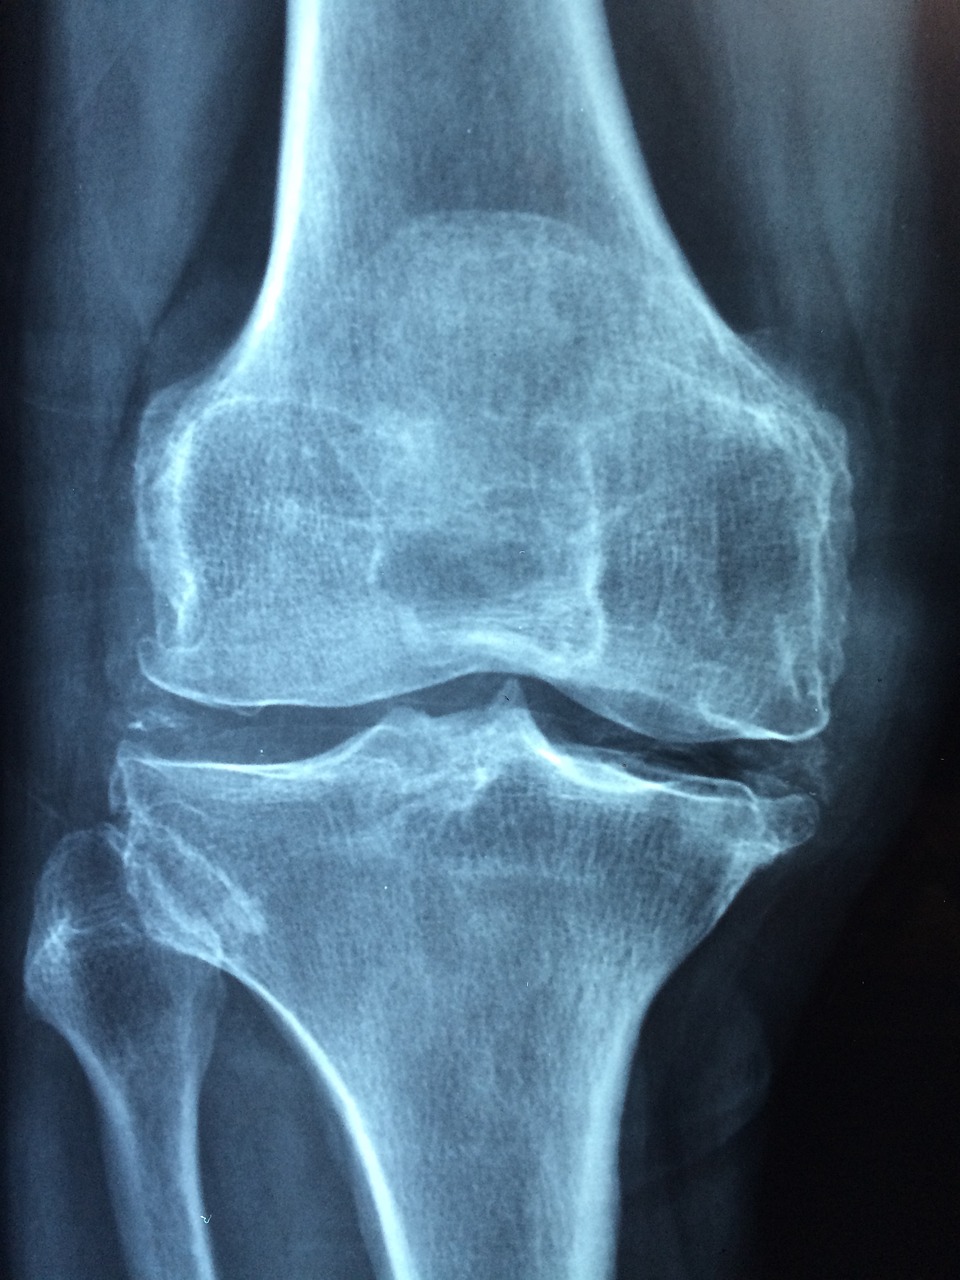

골다공증, 골다공증 원인 및 예방법 알아보기 본문

골다공증

골다공증은 전 세계 수백만 명의 사람들, 특히 여성과 노인들에게 영향을 미치는 일반적인 질환입니다. 골다공증은 뼈를 약화시켜 뼈를 취약하게 만들고 골절되기 더 쉽도록 만듭니다. 골다공증의 원인, 증상 및 치료 방법을 이해하는 것은 예방과 관리에 매우 중요합니다.

골다공증이란 무엇인가요? 골다공증은 뼈의 질량이 낮아지고, 뼈조직이 악화되는 것을 특징으로 하는 진행성 뼈 질환으로, 뼈의 취약성과 골절에 대한 취약성을 증가시킵니다. 골다공증의 영향을 받는 뼈는 유해하고 약해져, 실제로 경미한 연쇄 작용이나 외상을 잠재적으로 위험하게 만듭니다.

골다공증의 진단 방법

- 골밀도 검사(DXA Scan): 이 비침습적 검사는 엉덩이, 척추 등 다양한 부위의 골밀도를 측정하여 뼈 건강을 평가하고 골다공증을 진단합니다.